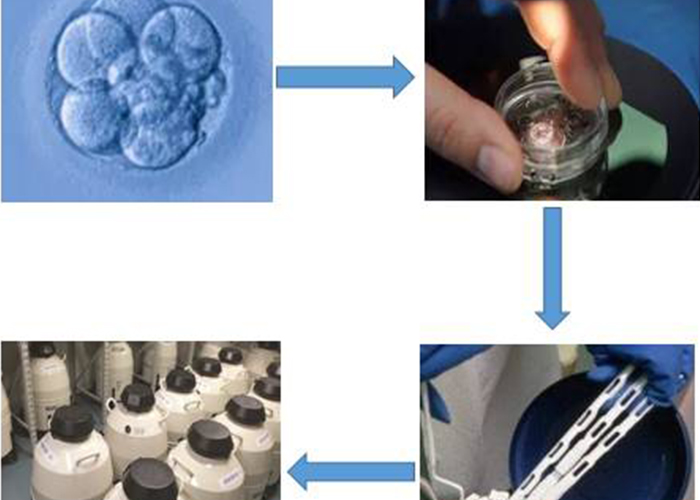

来了解一下胚胎冷冻的过程:

将新鲜的剩余胚胎放置入玻璃化冷冻液中,也就是培养皿中,里面含有胚胎生长发育所需的各种营养成份。

冷冻液会在胚胎周围形成一圈保护层,冷冻液会渗进胚胎,替换出其中的水份。

待其保护完成后将胚胎从培养皿中转入到更容易冷冻保存的杆内。

最后将冷冻载杆放置到液氮罐中,使胚胎在冷冻液的保护下完全沉睡,等再需要的时候再解冻移植。

图为胚胎冷冻过程